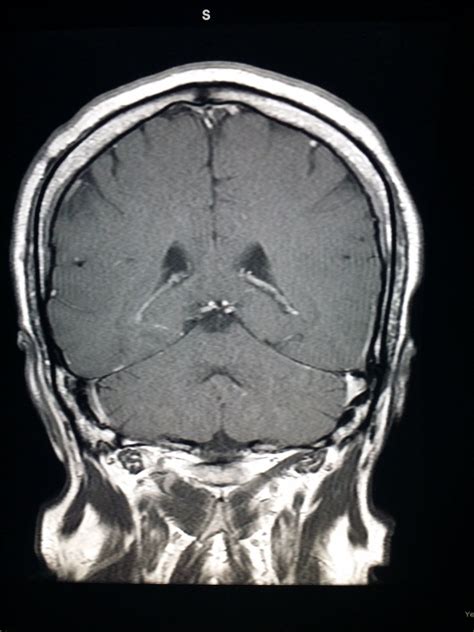

4k00:20mri brain or magnetic resonance imaging in coronal view comparison t1 vs t2 showing anatomical of the brain. T2 weighted, for those that like to know about that. View of mri scanner and the basic parts of mri scanner. On axial scans, it is the part of the temporal cortex that is immediately lateral to the pons. Brain scans from magnetic resonance imaging experiments (mri) have been a popular choice with the number of… the focus of these posts will be on the structure and analysis of the data and not on the underlying principles of magnetic resonance imaging. A hierarchical clustering algorithm was applied to magnetic resonance images (mri) of a cohort of 751 subjects having a mild cognitive impairment (mci), 282 moreover, the differences were strikingly unidirectional in all brain regions displaying marked differences. Coronal view images going through the anterior (a,b), middle (c,d), and posterior part (e,f) of the brain at 17 gw. Revise the mri images of the brain and learn the brain mri basics now at kenhub!

Advanced brain tumour segmentation from mri images. This is a 100 micron resolution magnetic resonance imaging (mri) scan of an ex vivo human brain specimen. The module on the anatomy of the brain based on mri with axial slices was. Coronal and sagittal views of the. The anatomy of the brain is studied by means of axial, coronal and sagittal views. This mri brain coronal cross sectional anatomy tool is absolutely free to use. The sagittal images are scaned perpendicular to the coronal scan. The application of magnetic resonance imaging has evolved rapidly since its clinical development in the early 1980s. The visual comparison of mri brain tumor segmentation results. Normal mri brain coronal images. Currently, the sbd contains simulated brain mri data based on two anatomical models: This weighted sum strategy is conductive to select most valuable information automatically from dierent eld of view. Color enhanced coronal (frontal) view of what a normal brain looks like.

Mri atlas of the brain coronal view of brain. A hierarchical clustering algorithm was applied to magnetic resonance images (mri) of a cohort of 751 subjects having a mild cognitive impairment (mci), 282 moreover, the differences were strikingly unidirectional in all brain regions displaying marked differences.